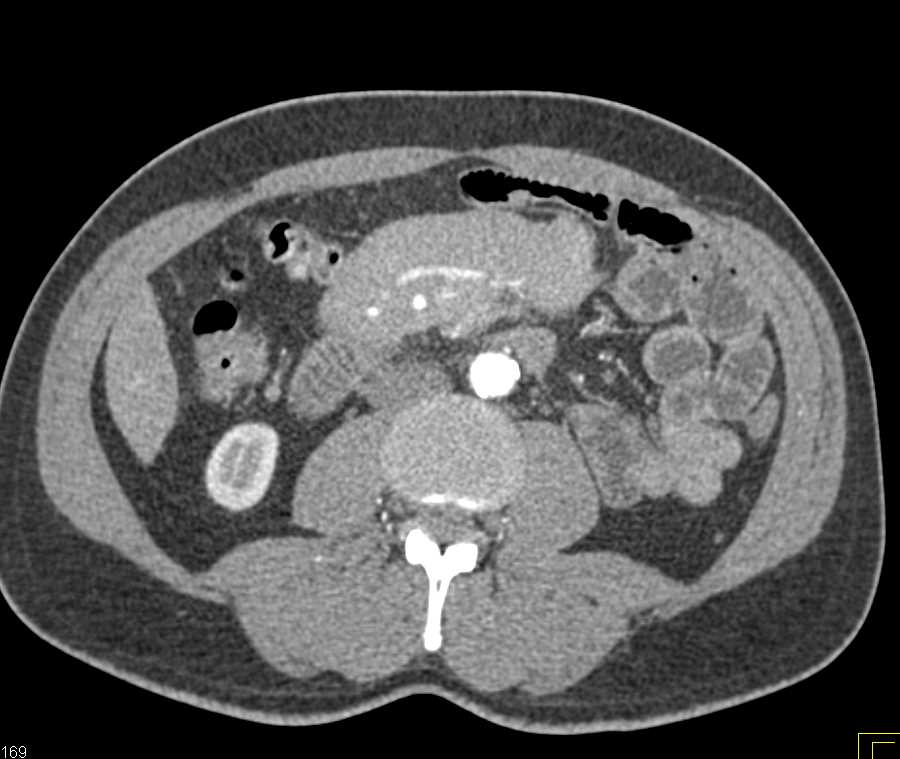

Pseudomembranous Colitis Right Colon